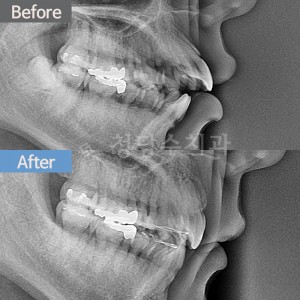

치료전후사진 1 페이지 | 대전청담수치과 - 둔산동치과, 대전치과, 대전교정치과, 대전임플란트